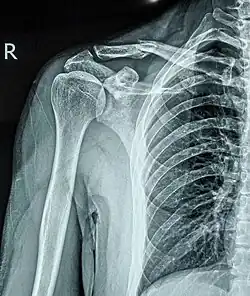

Перелом ключицы — патологическое состояние, проявляющееся нарушением анатомической целостности ключицы. Чаще всего переломы происходят в средней трети на границе наружной и средней третей ключицы, на наиболее изогнутой и истончённой её части. Наиболее часто встречающиеся — косые и оскольчатые.

Составляет 2,6-12 % от всего числа переломов, 44-66 % переломов плечевого пояса. В 80 % случаев перелом происходит в средней трети, 15% — перелом акромиального конца ключицы, 5 % — стернального (грудинного).

Выполняется рентген в прямой и боковой проекциях.